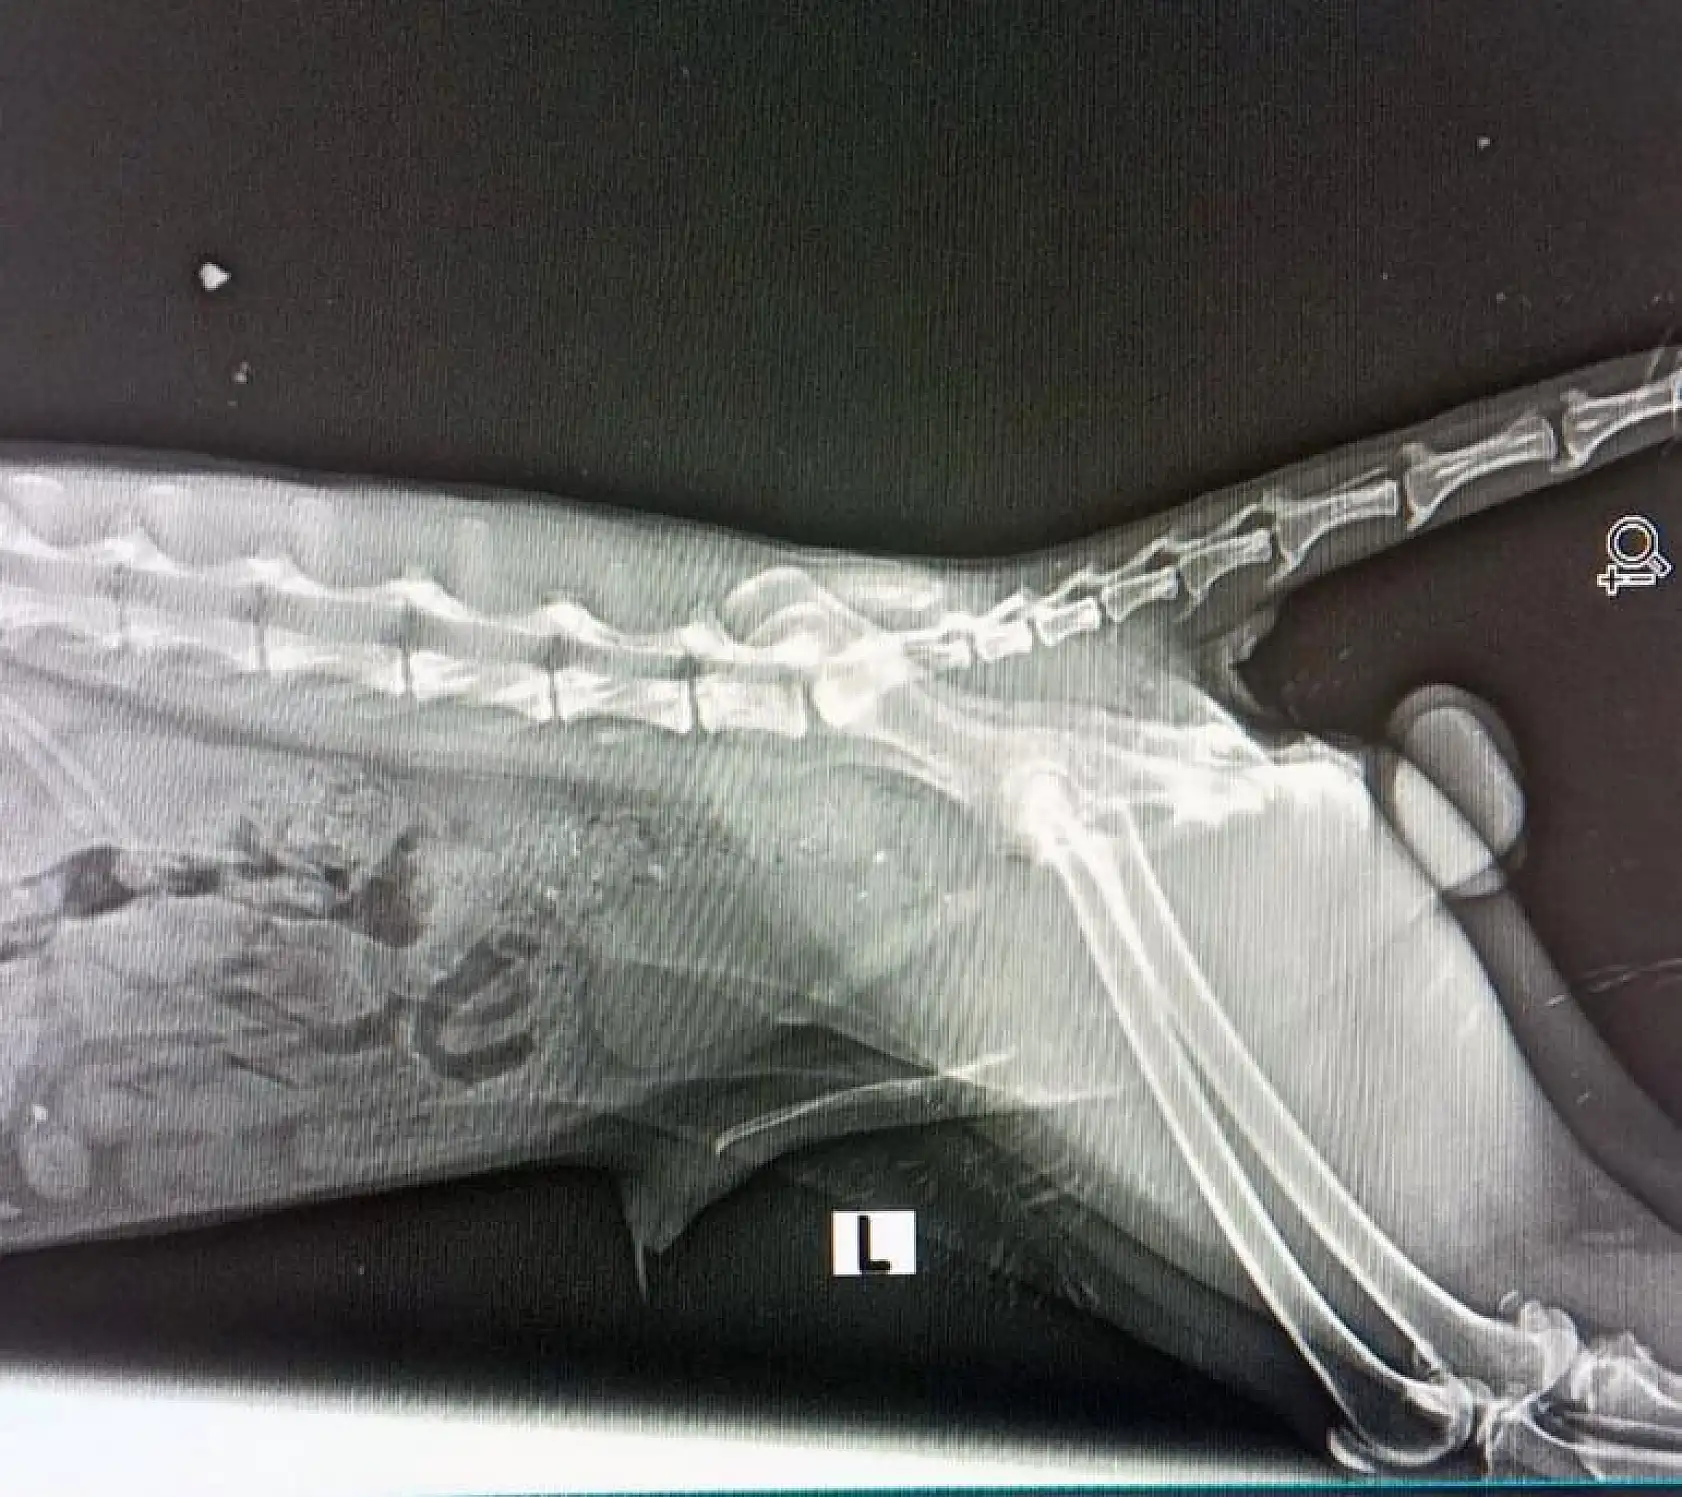

Muğla'nın Datça ilçesinde arka ayaklarından yaralı vaziyette bulunan Tilki, ekipler Doğa Koruma Milli Parklar Datça şefliği ekibi tarafından hayvan hastanesinde tedaviye alındı.